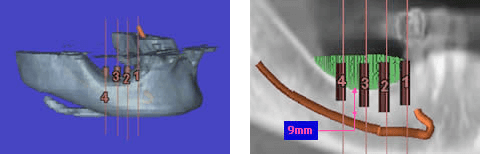

インプラント治療を希望し来院され、全顎的に高度の骨吸収を認めました(図1)。術前のCTデータをSimplantsにより3D構築し診断・計測したところ、下顎左側臼歯部の歯槽骨頂-下歯槽菅距離は第一第二大臼歯部で約9mmと近接、(図2)また、同部のハンスフィールド値からは歯槽頂部における皮質化の昂進を認めました(図3)。インプラント埋入には垂直的な骨高径獲得が必要不可欠であることから、vertical ridge augmentationを予定すると共に再生すべき垂直的骨量が約8mmであること、および同部の骨質から難易度の高さが予想されます(図4)。

図2:Simplantsによる診断3D画像

図3:欠損部歯槽頂のHounsfield値